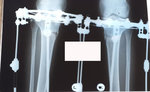

Дата операции 23.01.2015г.

Дата снятия аппаратов 28.04.2015г.

Срок лечения 95 дней.